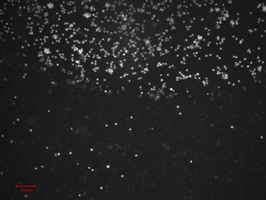

The photodynamic effect of the conjugate proposed is depicted in Figure 3. Based on propidium iodide fluorescence, the difference of cells state is shown in irradiated (upper part of Figure 3) and non-irradiated areas of nanoconjugate treated cells suspension. As it can be seen, the irradiation has led to massive cases of cell death proving enhanced photosensitizing activity of the nanoconjugate.

Figure 3 Photodynamic activity of Chl.e6-ND-Ab conjugate Irradiation border in the sample (PI fluorescence).